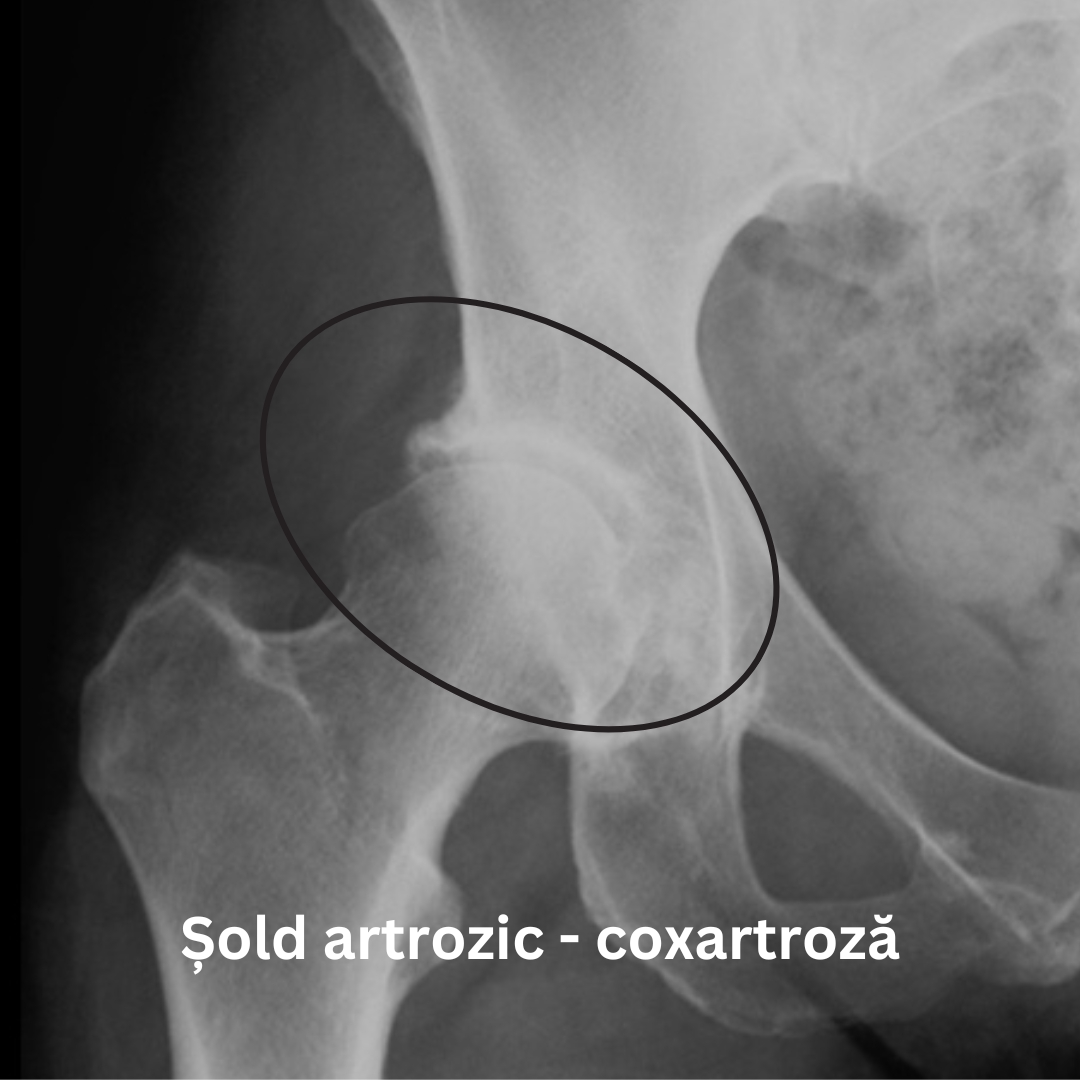

- Radiografii – acestea arată modificările structurale ale articulației, cum ar fi îngustarea spațiului articular și prezența osteofitelor.

Radiografia unui șold artrozic poate arăta o îngustare a spațiului articular, modificări ale osului, precum și formarea de osteofite (imaginea din dreapta).

În cazul unui șold sănătos cartilajul articular are o suprafață netedă. Însă în situația în care apar anumite boli ale șoldului, cartilajul articular se deterioreză, iar un contact neted nu mai poate fi posibil.

Degradarea cartilajului este însoțită ulterior de deformarea capului și a acetabulului fapt ce limitează și mai mult mișcarea. Când cartilajul este complet distrus apare fenomenul numit comun “frecare os pe os”.